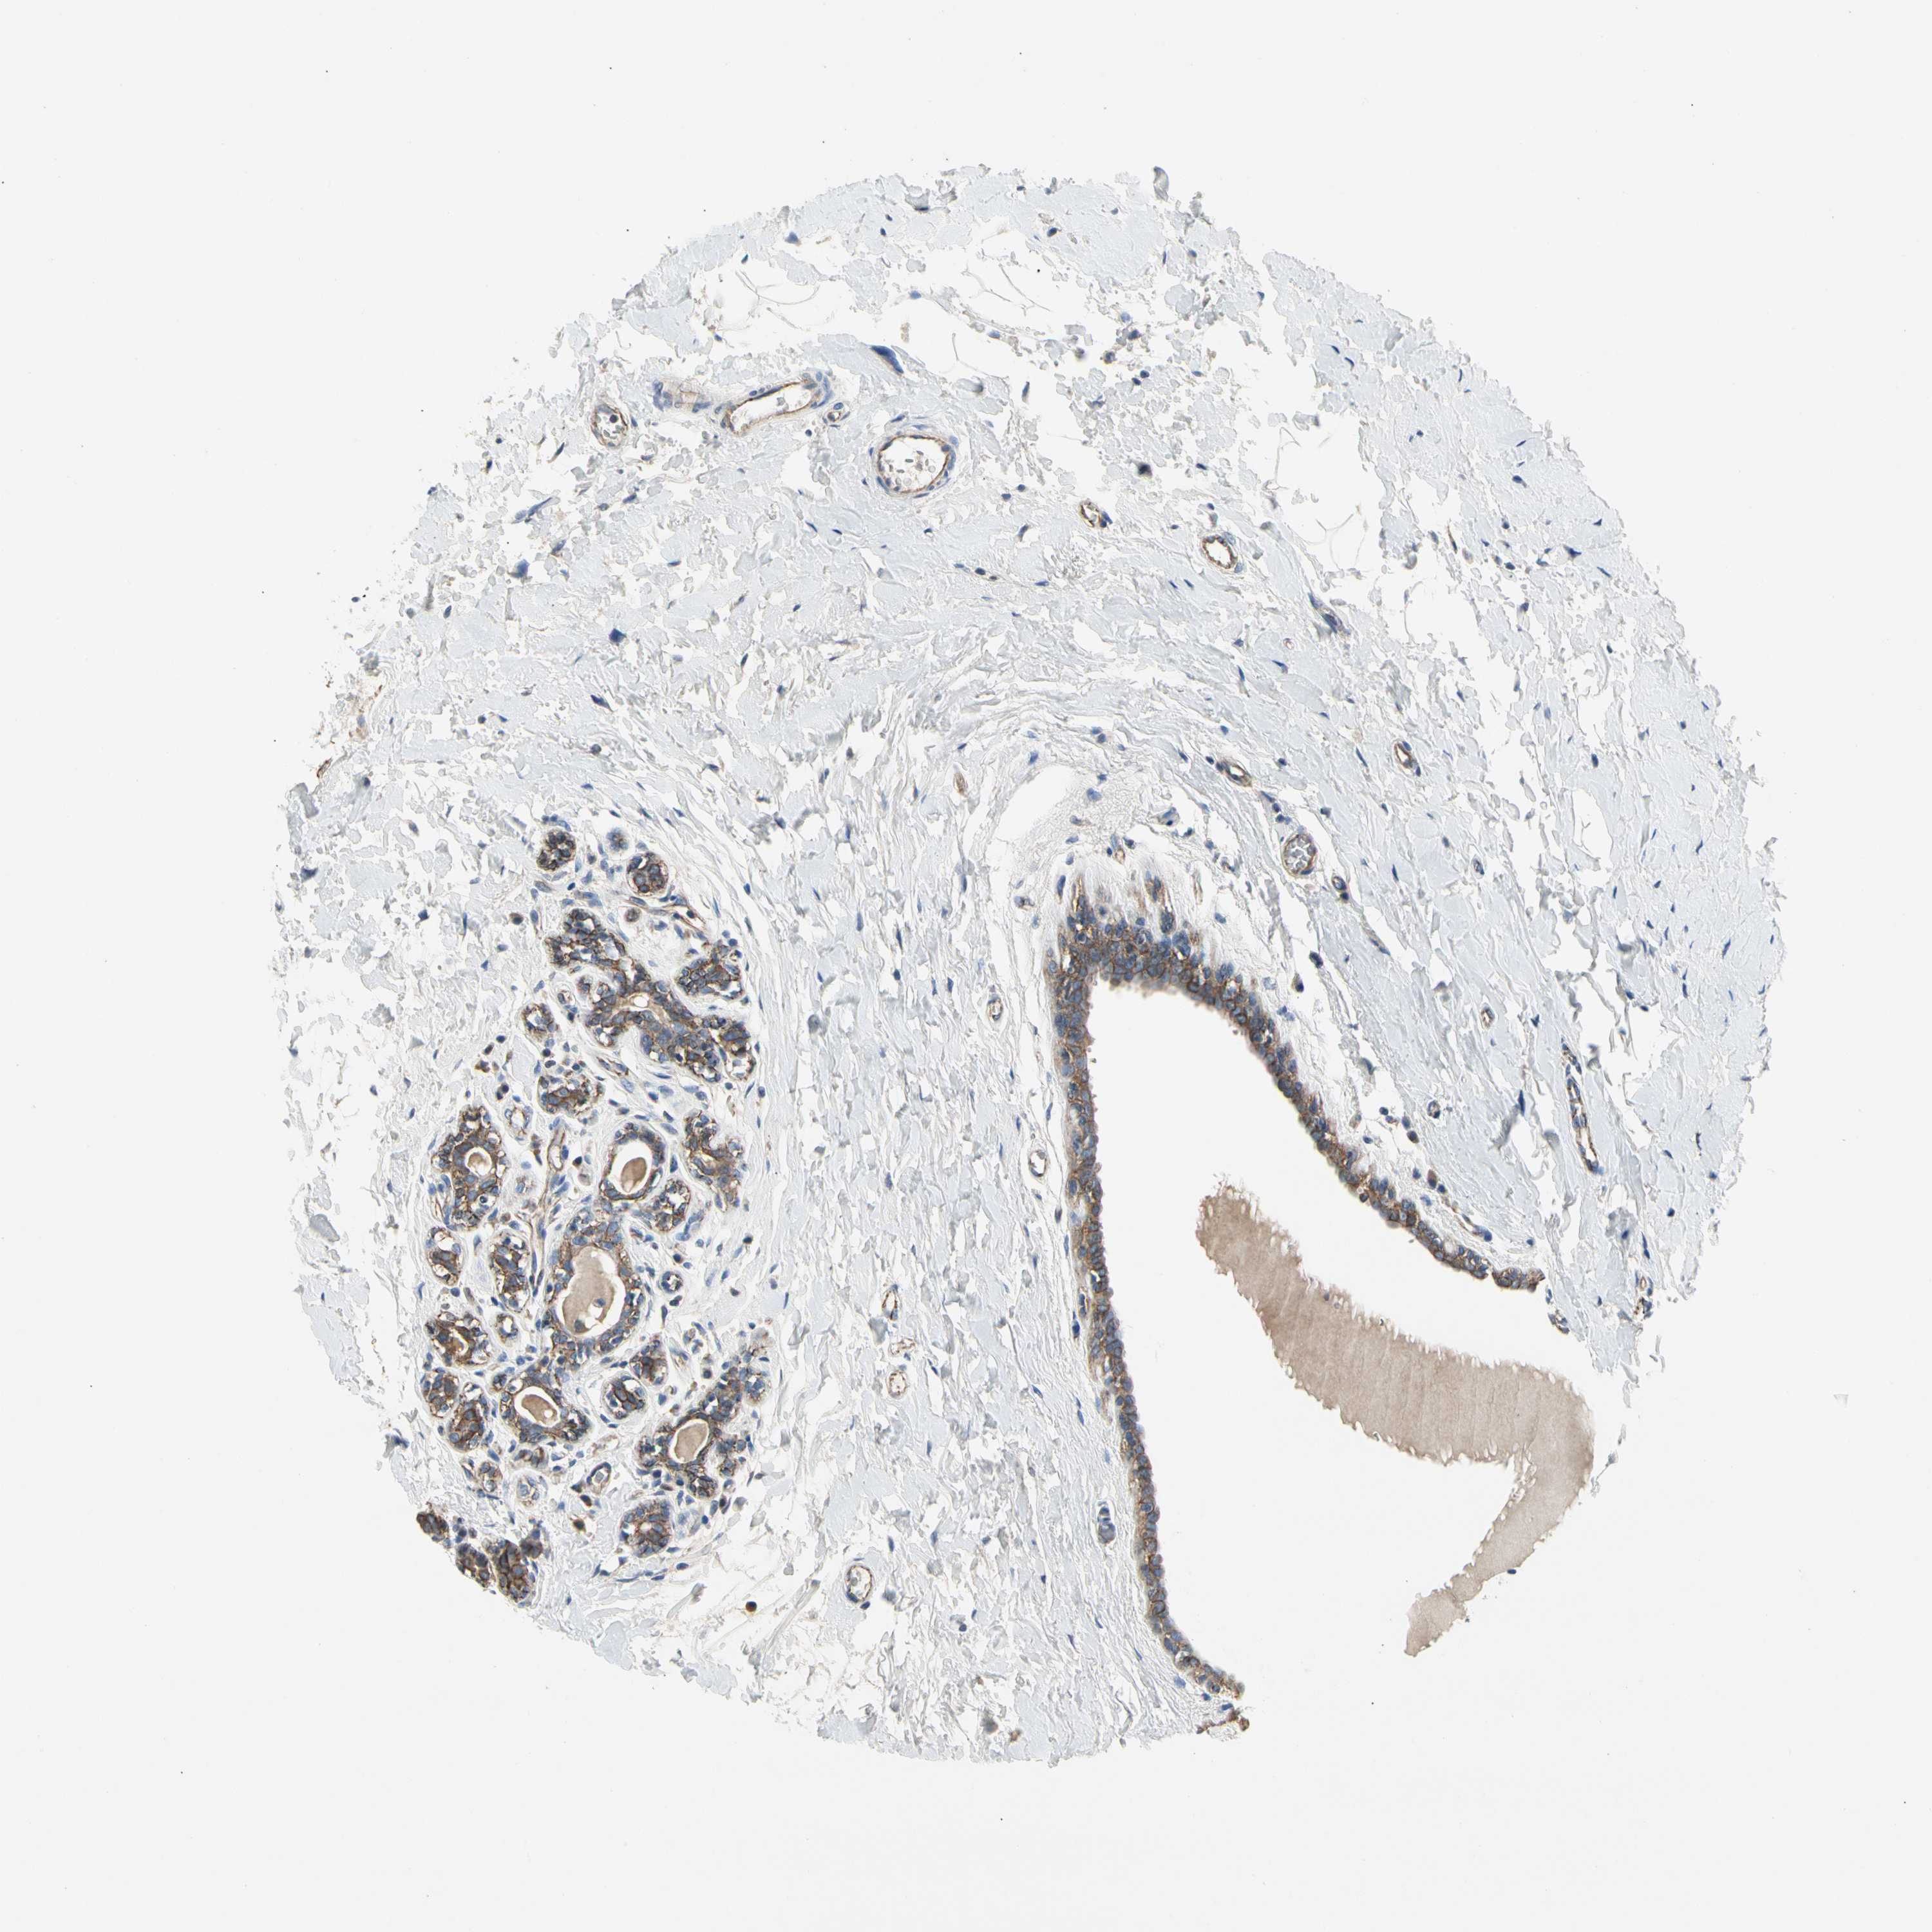

CANCER BREAST CANCER Show tissue menu

BRCA TCGA BRCA VALIDATION PROTEIN EXPRESSION

ANTIBODIES

AND

VALIDATION

LGR6 is potential prognostic, high expression is favorable in Breast Invasive Carcinoma (TCGA)